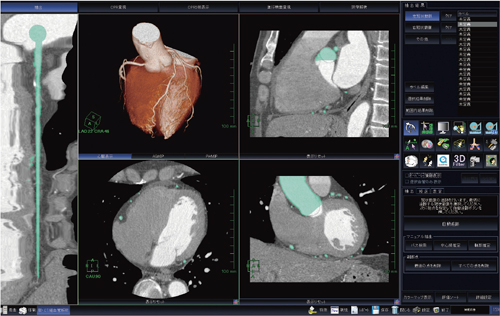

心臓CTにおける冠動脈解析ソフトウェアである“新・CT細血管解析”は,従来から冠動脈解析で使用されてきた“CT細血管解析”をまったく新しくリニューアルしたソフトウェアである。高い精度での冠動脈の自動認識はもちろんのこと,大動脈・左右冠動脈・心臓それぞれがセグメンテーションされた状態で認識されるため,ソフトウェアが起動するとすぐにVR,coronary tree,angiographic viewなどを切り替えるだけで画像表示することが可能となった(図1)。

図1 “新・CT細血管解析”初期画面